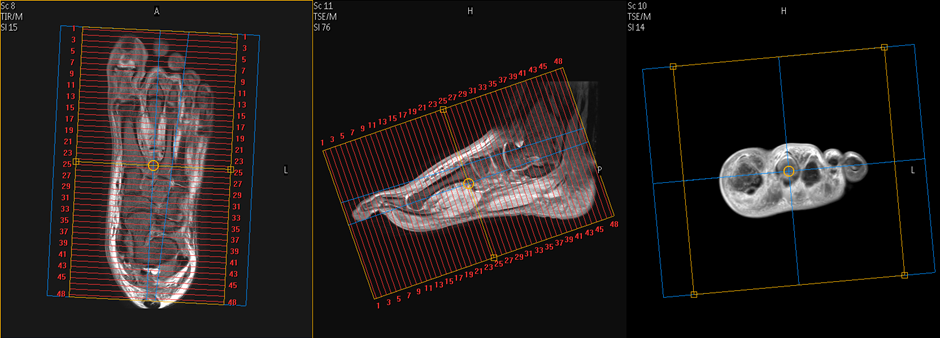

FOOT

Position : Supine ,Feet first

Centre laser beam on mid ankle joint

Sequence : sagittal pd FS

Coronal : PD FS,T1,T2,PD

Transverse : PD FS,T2,T1.GRE

Coronal: plan line perpendicular to meta tarsal bone & check box angle on other planes in appropriate angle.

Transverse: plan :On sagittal image block  line parallel  to metatarsal or phalanges bone & check the block angle on other planes in appropriate angle.

Sagittal: plan : on coronal image block  line parallel  to metatarsal or phalanges bone & check the block angle on other planes in appropriate angle.